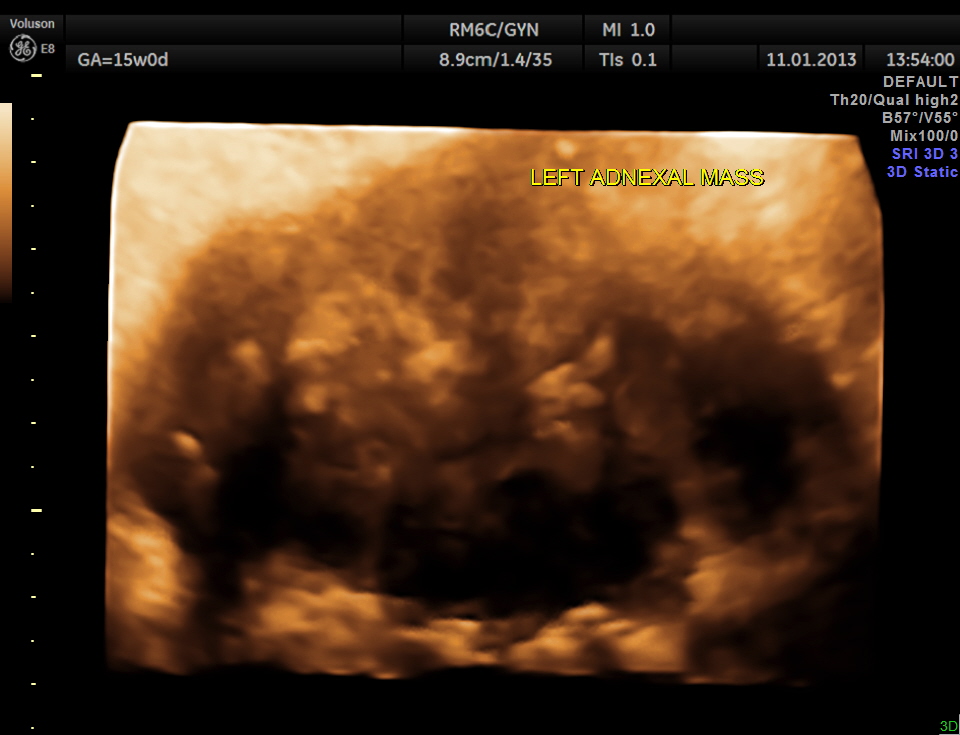

3 D reconstructed image of the left adnexal mass.

So this patient was taken up for surgery because of the clinical presentation of acute pain , probably torsion. The mass lesion was removed and the pathologist reported it as PARA OVARIAN FIBROMA . The pregnancy was continued normally and was uneventful . The fetus showed mild bilateral pelvi ectasis persistently from 28 weeks onwards till delivery. Scan done 1 month after delivery showed normal kidneys in the child.